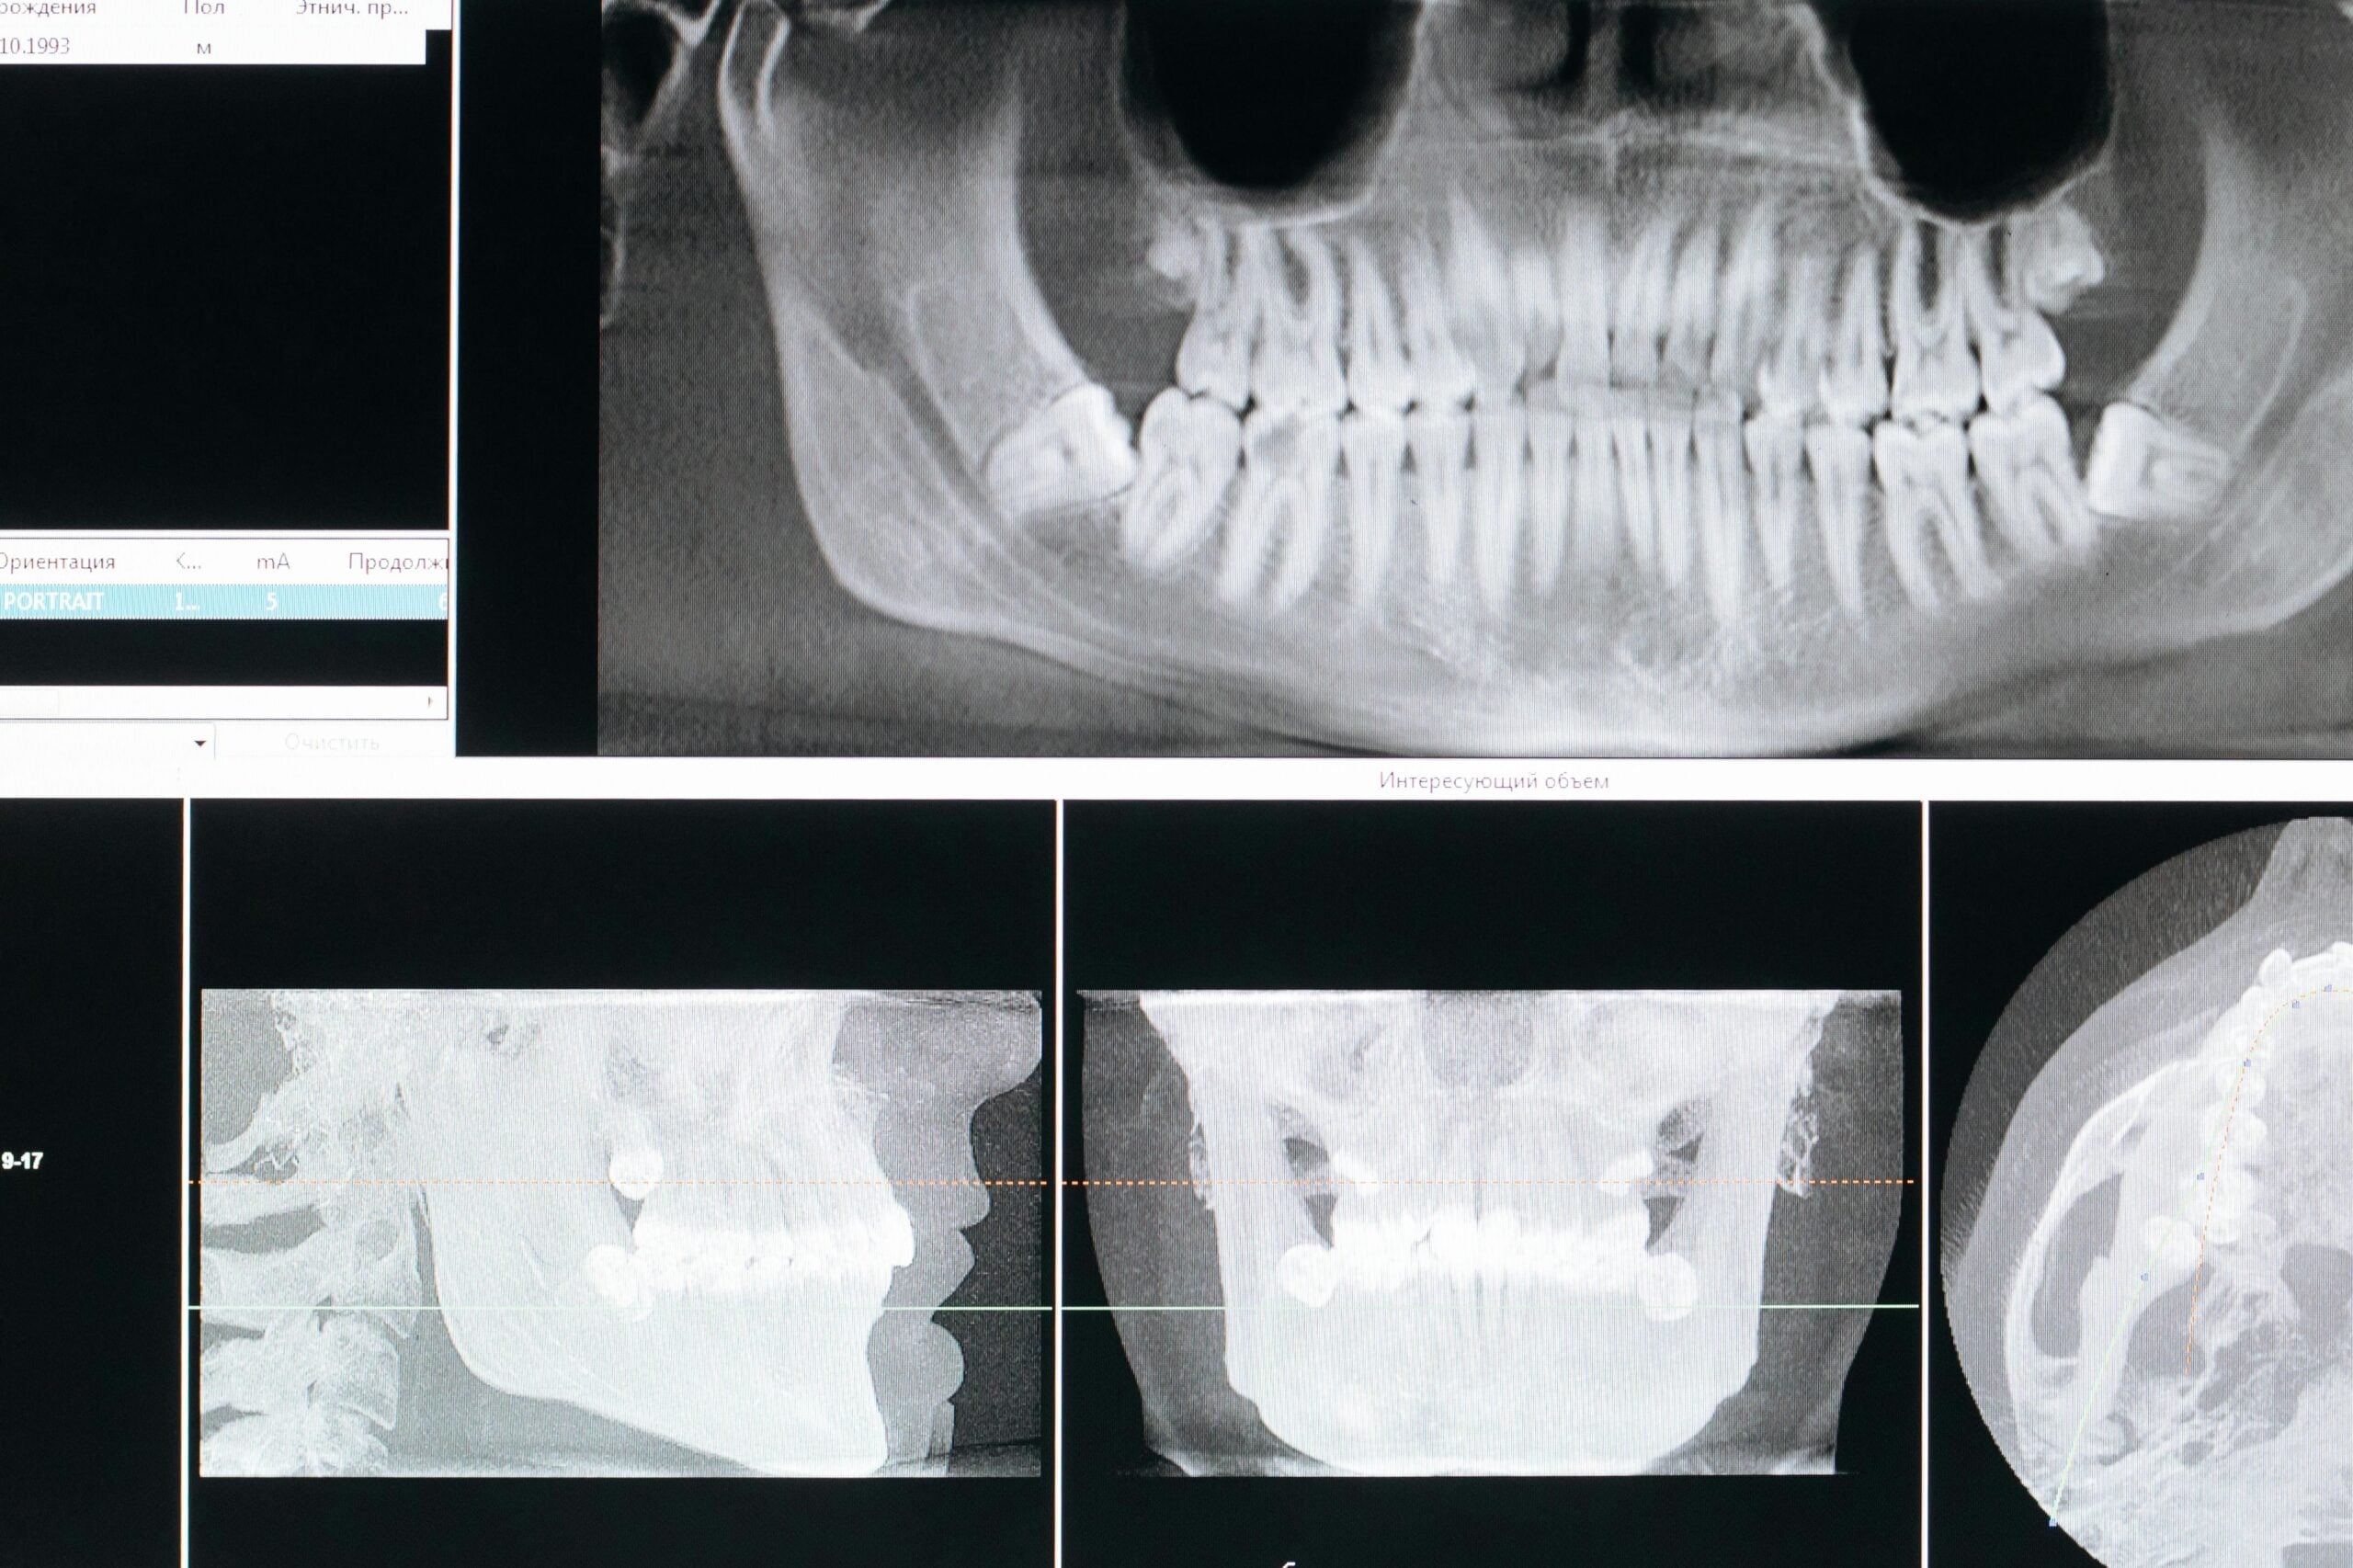

As we’ve seen, getting as much information as possible is critical to rendering a complete diagnosis. Naturally, we can’t diagnose what we can’t see, so it is important that we image the entirety of every tooth. In most cases, nothing accomplishes this better than an FMX. Below is an image of the same patient as before, this time we took an FMX.

Many things are now visible that hadn’t been seen in any of the previous x-rays over the last 5 years. Most importantly, this patient has advanced periodontitis, with several teeth in need of extraction. This patient came in for some fillings. Imagine his surprise when I explained the need to remove teeth and give him some form of denture in the future.

In the image above, I’ve marked the patient’s current bone level in red. The blue line is an approximation of where the bone level is supposed to be. As you can see, he has lost bone everywhere, but the top left is particularly bad.

This patient’s bone loss was probably from a combination of factors which are beyond the scope of this article. Naturally, with so much damage to the supporting bone, many of his teeth were quite loose. The patient was well aware of his loose teeth, but none of his previous dentists had identified the cause. Of course they hadn’t, they didn’t have the images they needed to see the problem!